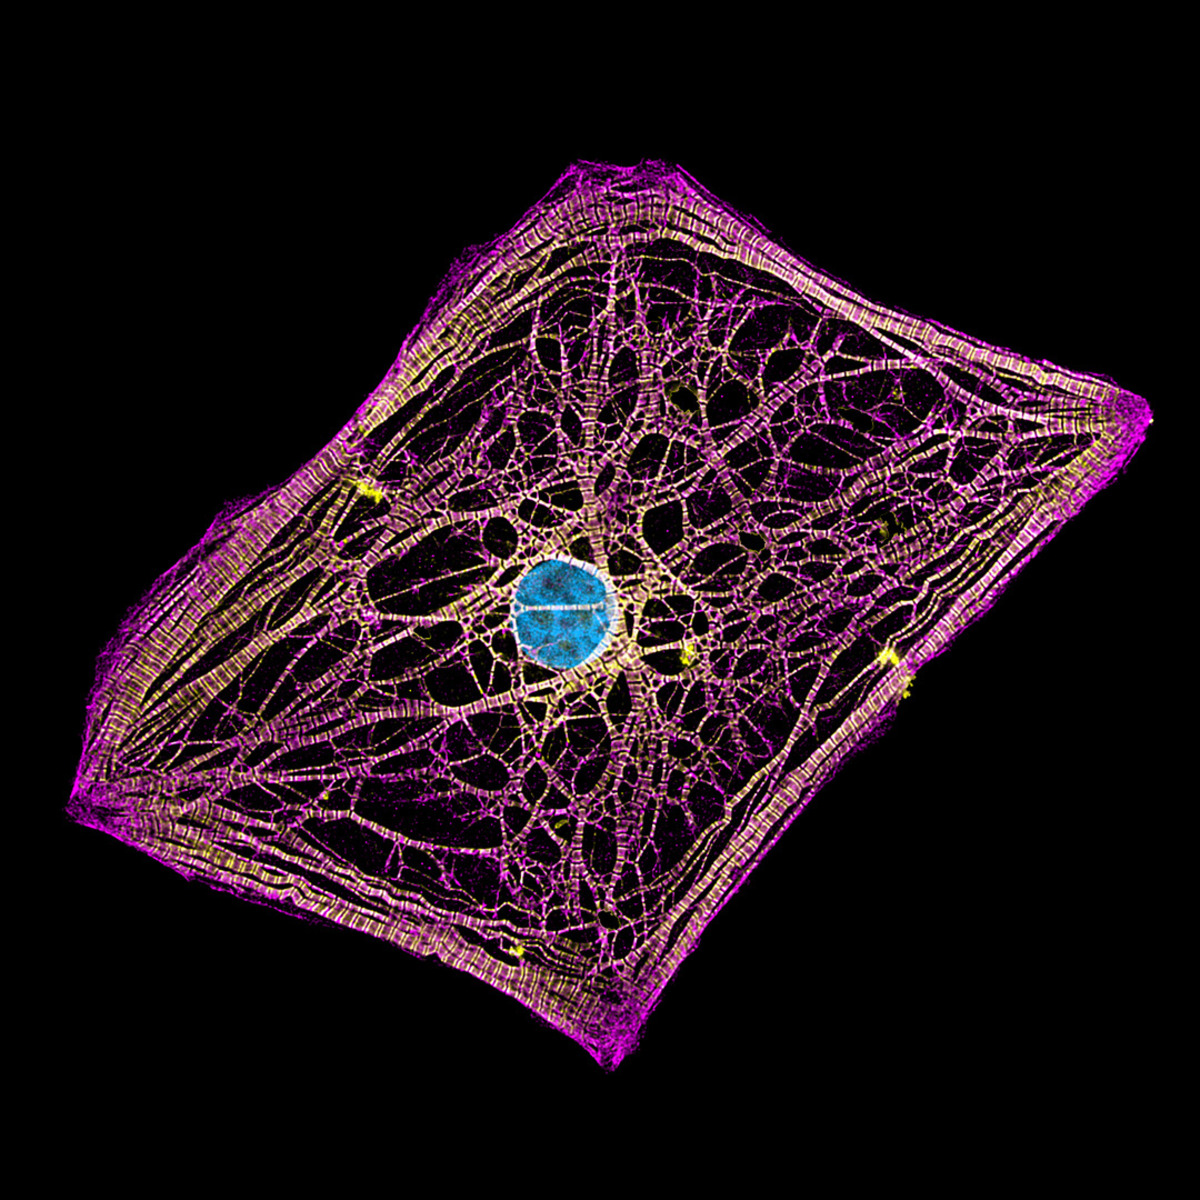

4. Ανθρώπινα καρδιομυοκύτταρα

Η φωτογραφία που κατέκτησε την 20η θέση ανήκει στους Hui Lin και Δρ. Kim McBride. Μέσα από ένα μικροσκόπιο μεγέθυνσης 60X, οι Lin και McBride αποτυπώνουν ανθρώπινα καρδιομυοκύτταρα (καρδιακά κύτταρα) που προέρχονται από επαγόμενα πολυδύναμα βλαστικά κύτταρα.